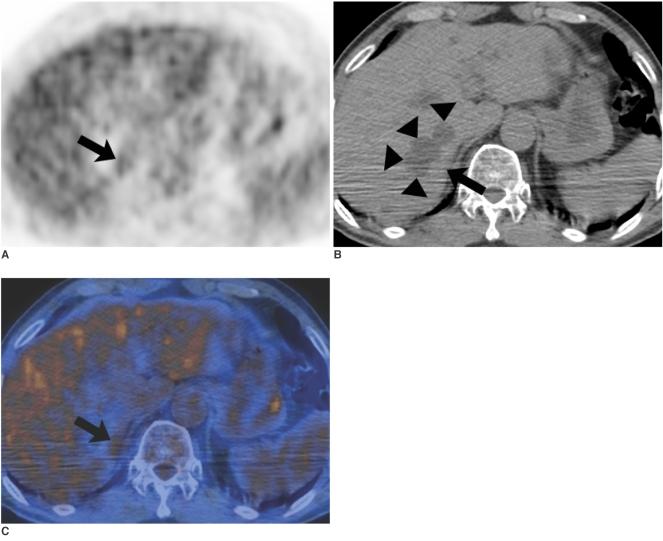

The aim of this study was to assess the diagnostic efficacy of integrated PET/CT using fluorodeoxyglucose (FDG) for the differentiation of benign and metastatic adrenal gland lesions in patients with lung cancer and to compare the diagnostic efficacy with the use of PET alone.

Sixty-one adrenal lesions (size range, 5-104 mm; mean size, 16 mm) were evaluated retrospectively in 42 lung cancer patients. Both PET images alone and integrated PET/CT images were assessed, respectively, at two-month intervals. PET findings were interpreted as positive if the FDG uptake of adrenal lesions was greater than or equal to that of the liver, and the PET/CT findings were interpreted as positive if an adrenal lesion show attenuation > 10 HU and showed increased FDG uptake. Final diagnoses of adrenal gland lesions were made at clinical follow-up (n = 52) or by a biopsy (n = 9) when available. The diagnostic accuracies of PET and PET/CT for the characterization of adrenal lesions were compared using the McNemar test.

Thirty-five (57%) of the 61 adrenal lesions were metastatic and the remaining 26 lesions were benign. For the depiction of adrenal gland metastasis, the sensitivity, specificity, and accuracy of PET were 74%, 73%, and 74%, respectively, whereas those of integrated PET/CT were 80%, 89%, and 84%, respectively (p values; 0.5, 0.125, and 0.031, respectively).

The use of integrated PET/CT is more accurate than the use of PET alone for differentiating benign and metastatic adrenal gland lesions in lung cancer patients.